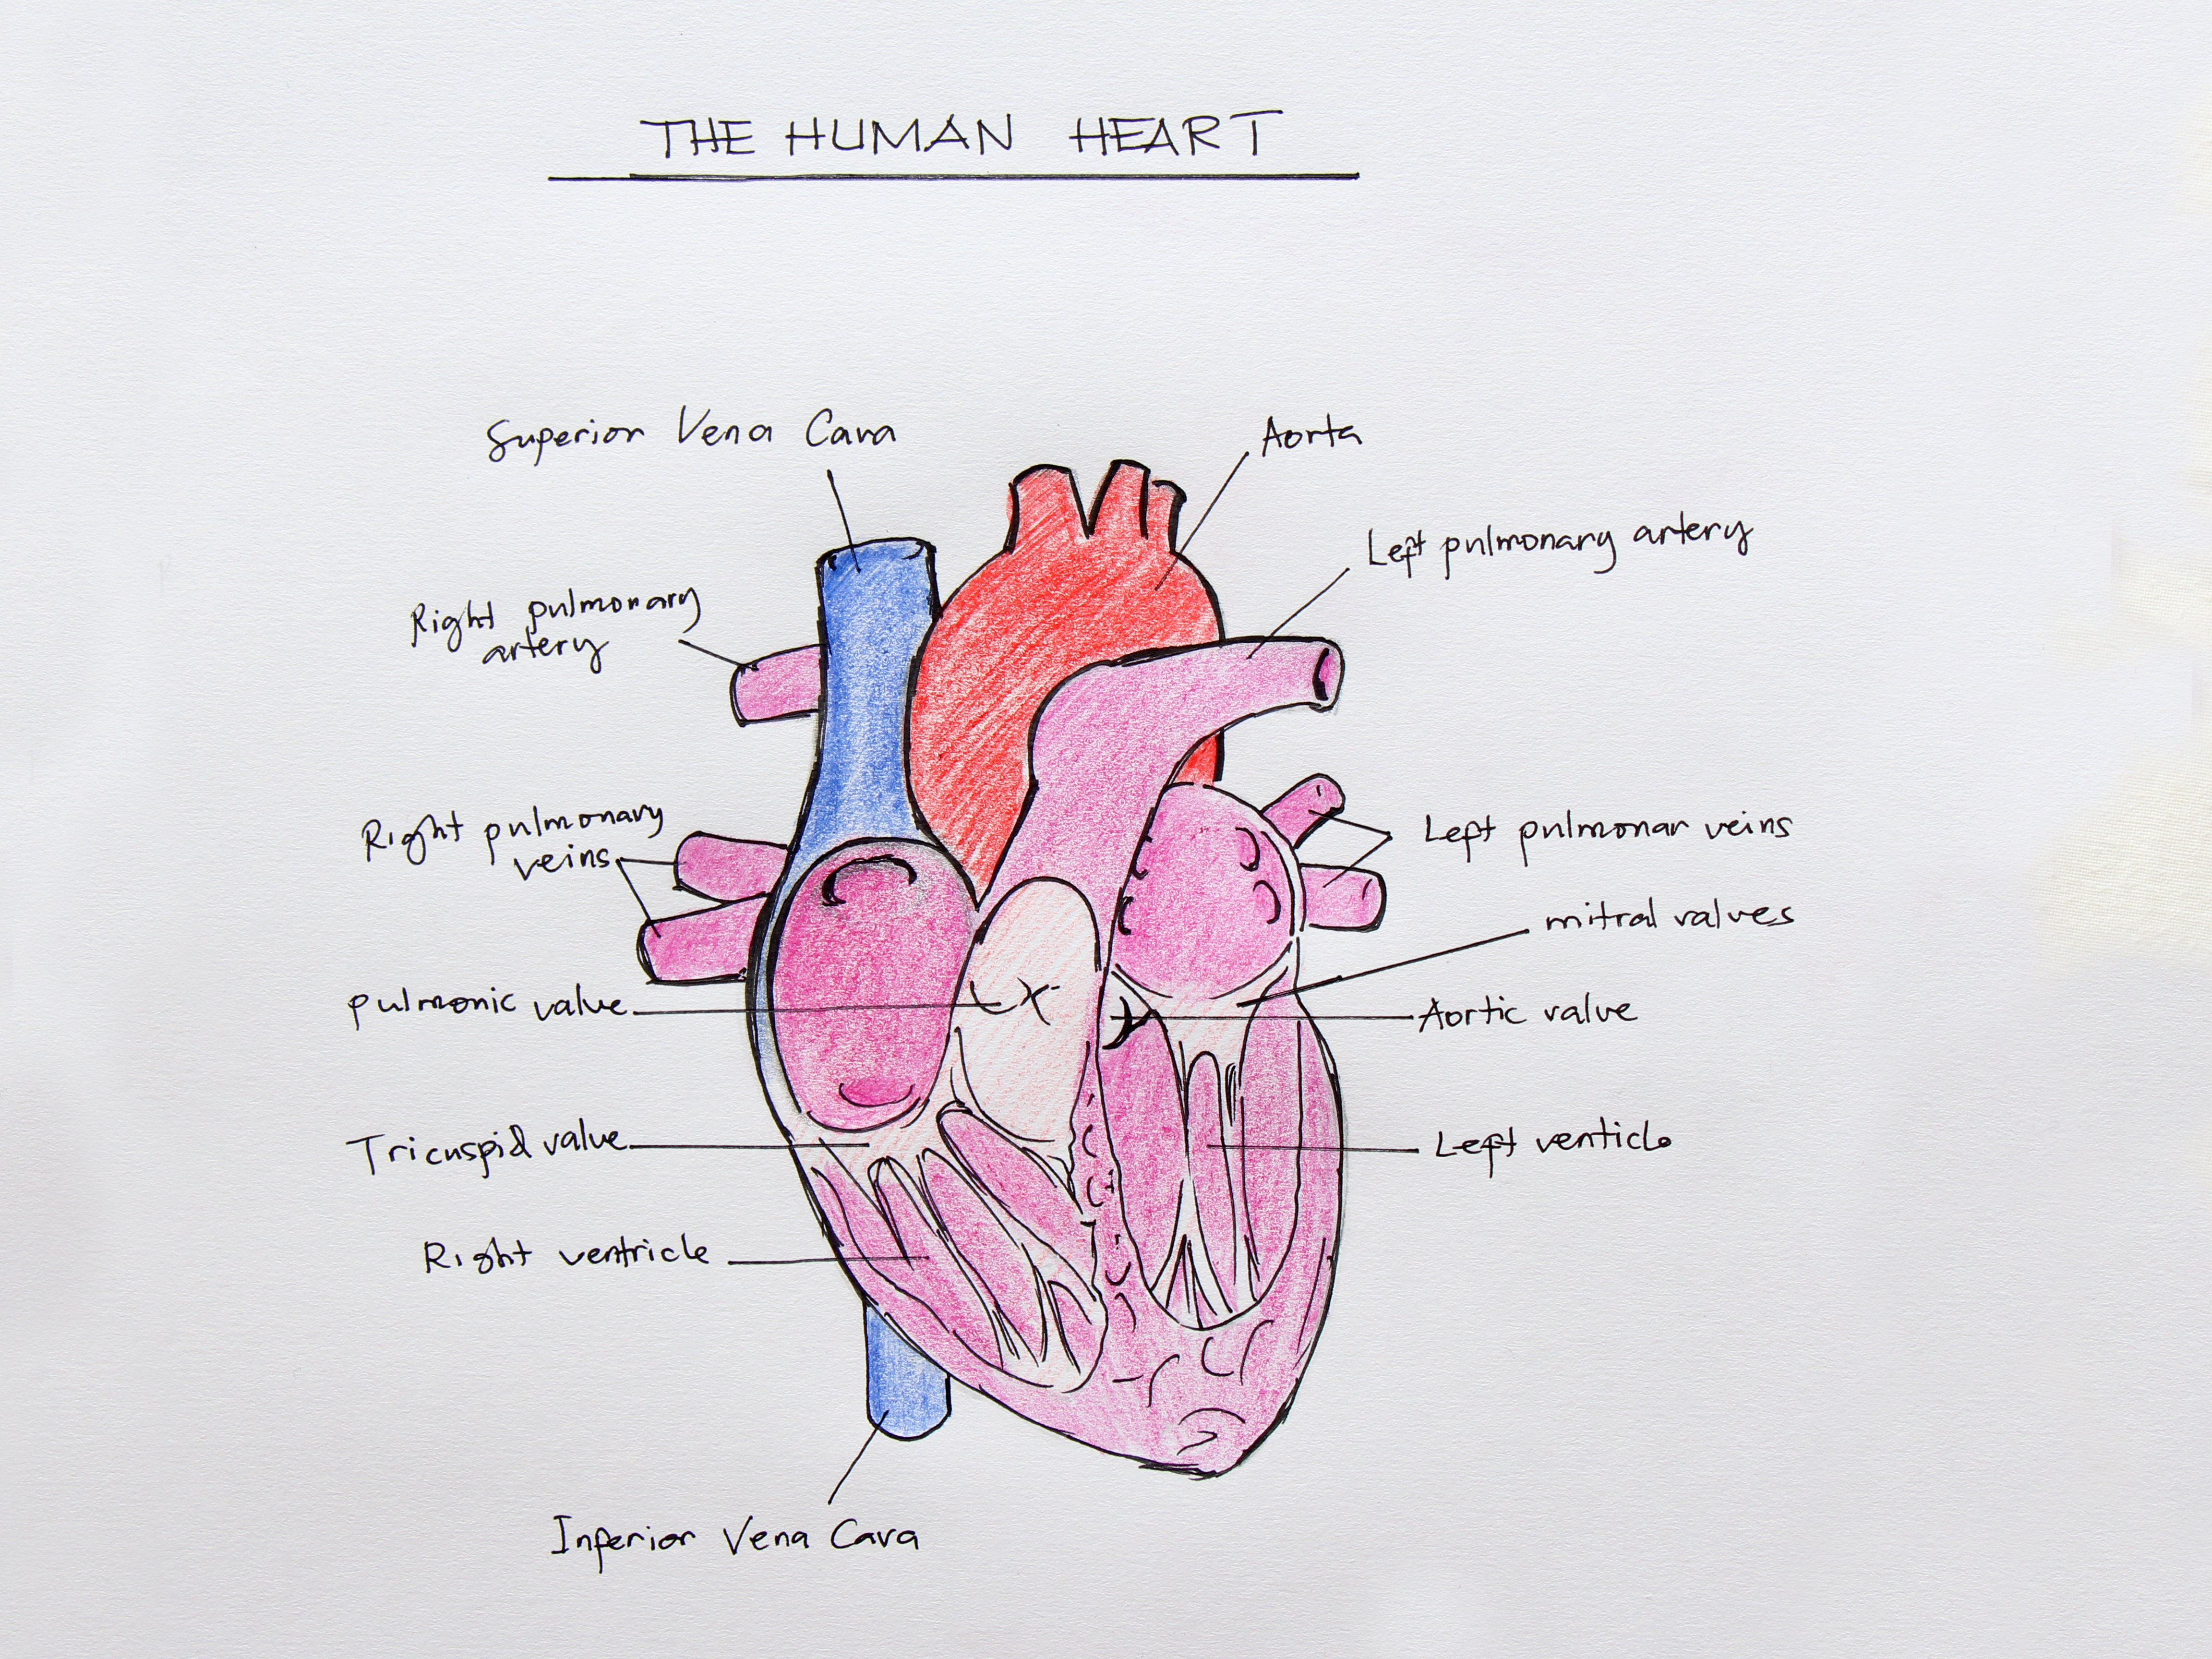

Heart Anatomical Drawing

Full color drawing pics

1500x904 Anatomical Drawing Of A Heart Anatomy Drawings Heart Medical

4608x3456 How To Draw The Internal Structure Of The Heart (With Pictures)